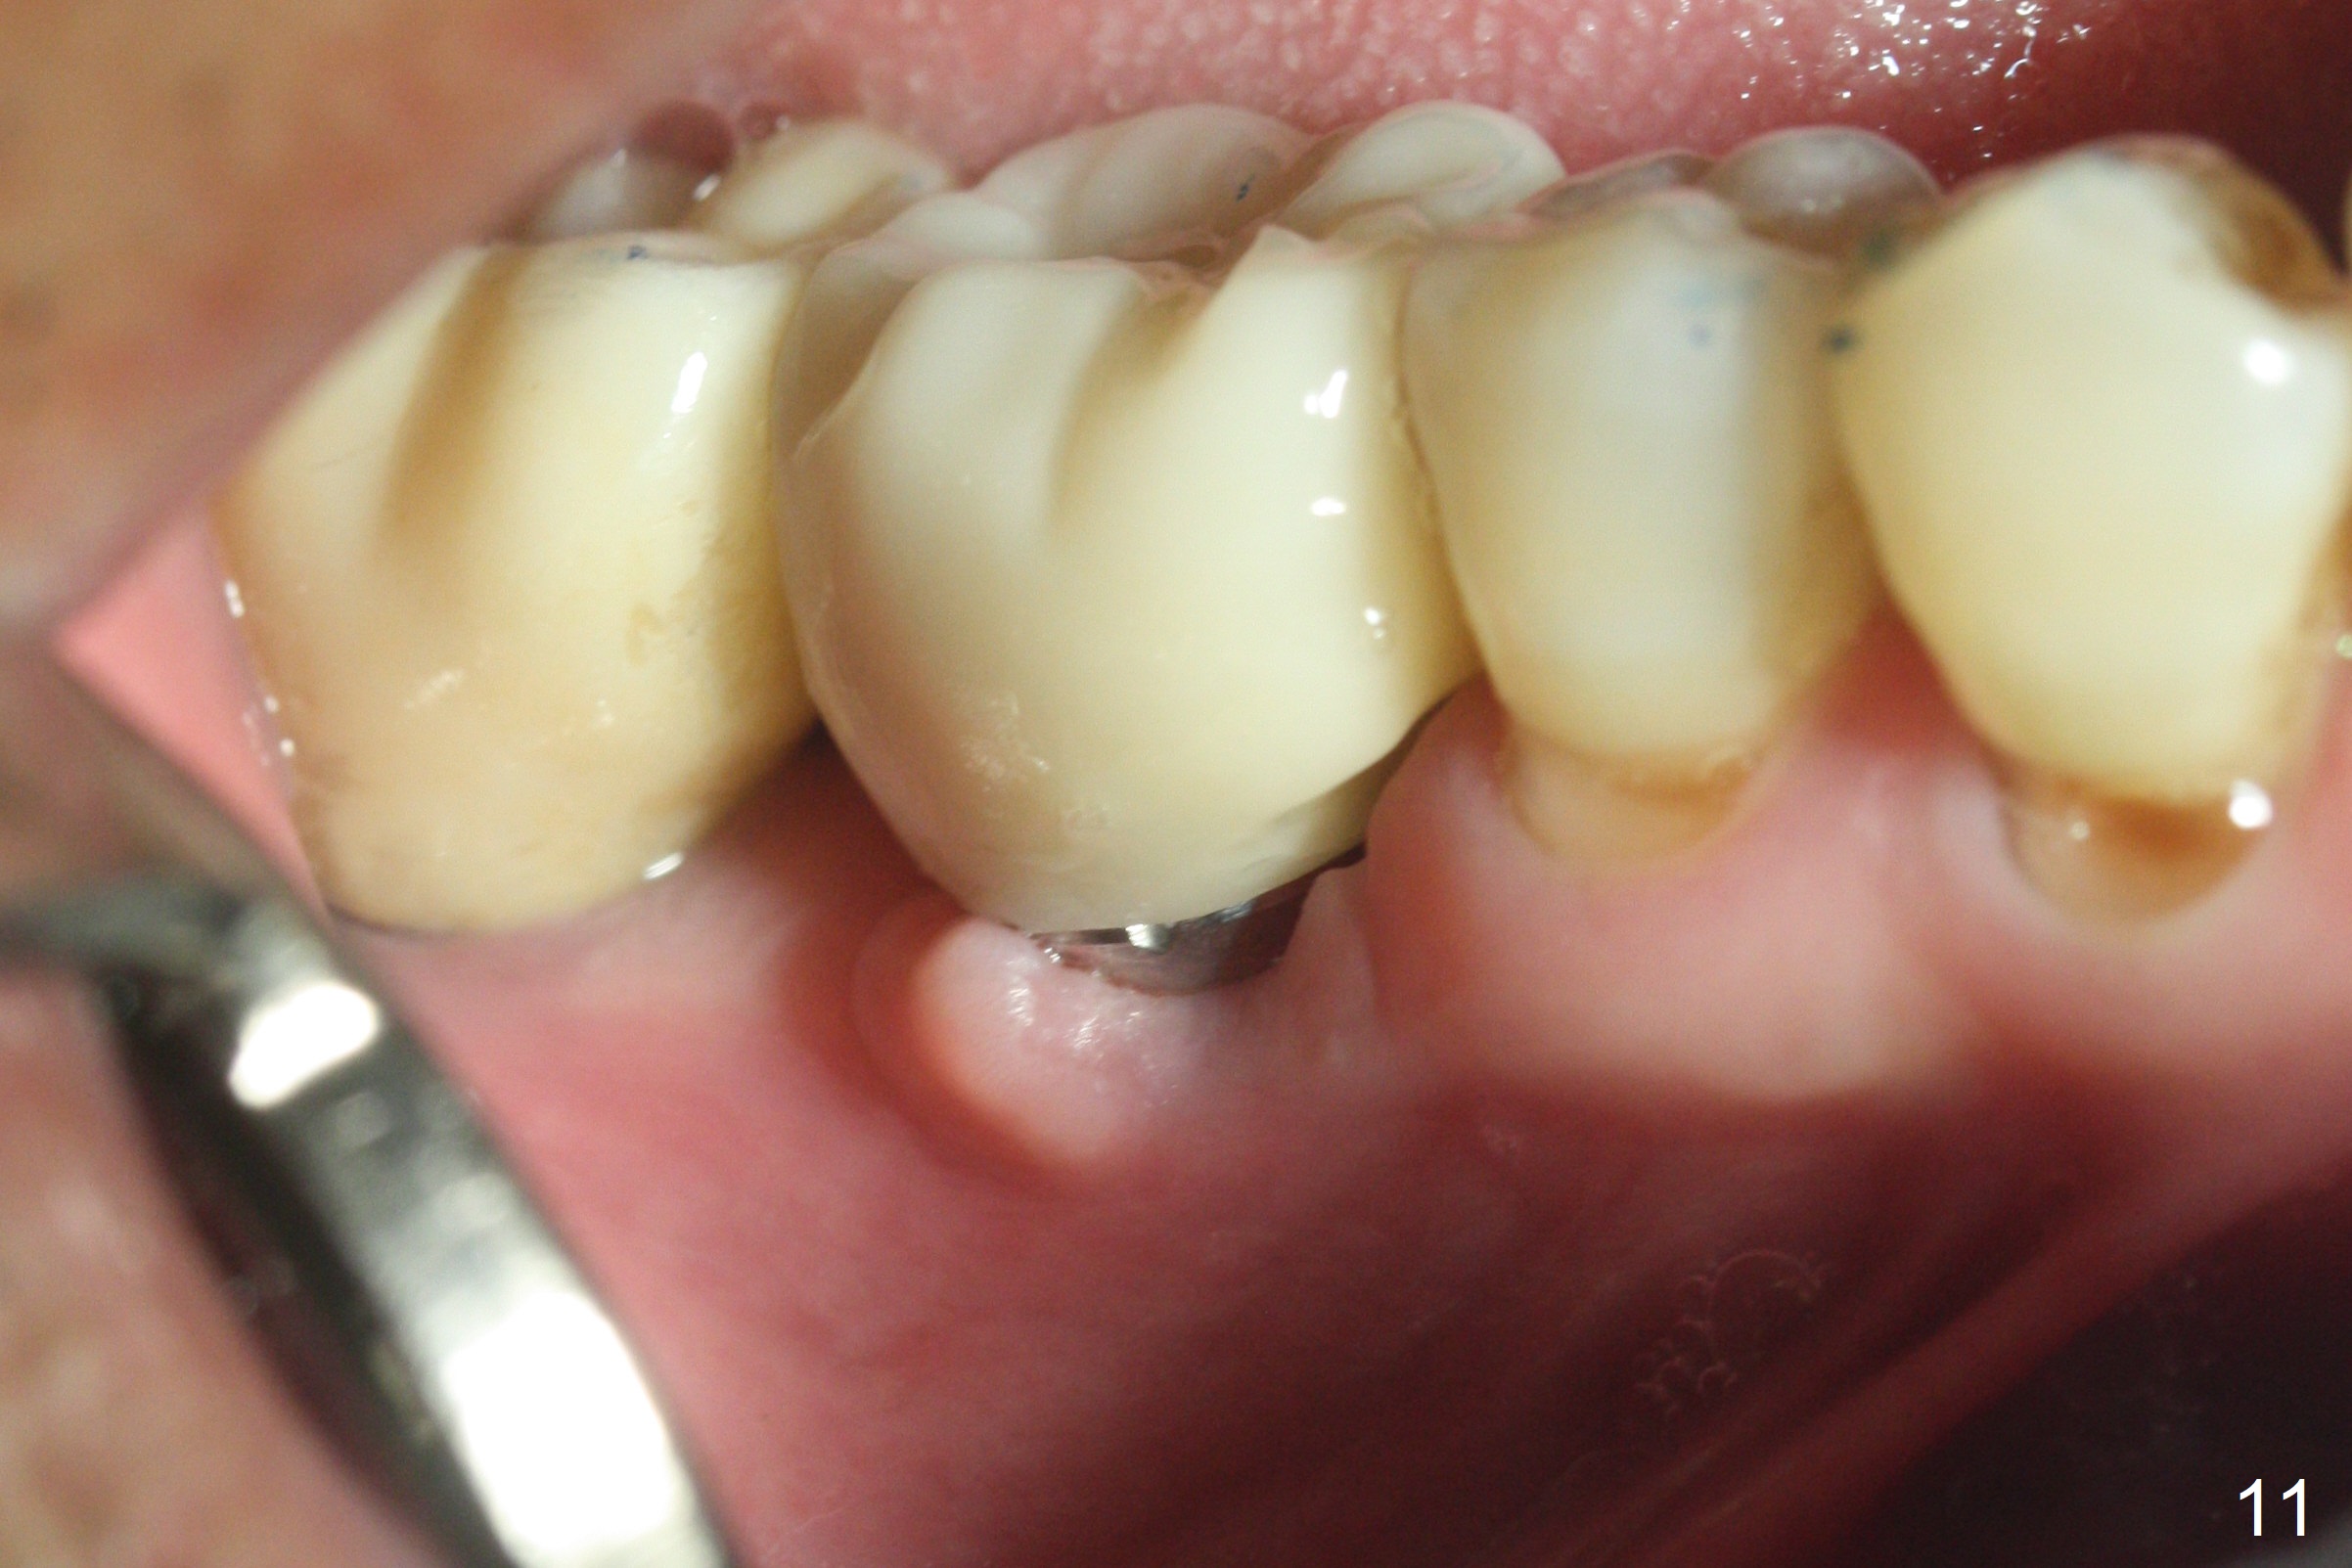

Extraction shows the large distal socket (Fig.1 D) and the thin and low septum (*) of the tooth #30. After Magic Split test confirms hard bone, osteotomy is initiated with 1.6 mm pilot drill with 11 mm stopper (Fig.2); there is 2.7 mm distance to the Inferior Alveolar Canal. Following Marking Bur, a 4.8 mm Magic Drill is used to finish the osteotomy with difficulty because of hard bone and ineffective local anesthesia due to infection. A 5x9 mm "dummy" implant is placed to determine the placement level relative to the distal crest (Fig.3 *). After removal of the dummy implant, an authentic one with the same dimension is placed with packing abundant allograft (.5-1.5 mm) and Osteogen (Fig.4 *); it appears that 4 to 5 threads (fins) of the implant (arrowheads) are engaged to the native bone for primary stability (>40 Ncm). Later more bone graft is placed distally (Fig.5 arrow). With the short implant placed not so deep, there is 6-7 mm clearance from the underlying canal (Fig.6). The patient is doing well 7 days postop (Fig.7). He feels that the provisional is too bulky buccally for the first 2 days postop. The buccal margin will be trimmed in another 2 weeks (dashed line). The patient in fact masticates on the right side postop. By the time he returns for provisional revision 1 months 10 days postop, he has mild pain. There is food entrapment. The provisional and the abutment are slightly loose, whereas the implant is stable with healing socket (Fig.8). A healing abutment is placed. The implant appears unstable nearly 5.5 months postop. The gap between the bone and implant seems to be large (Fig.9). The implant should have been larger and longer for fast healing. A healing screw is used instead. The site heals 10 months postop with an increase in bone density around the implant (Fig.10.) Prior to cementation of the final crown, the abutment is minimally exposed (Fig.11 (6.5x5.7(3) mm)). In fact the abutment screw becomes loose 2 months post cementation (1 year postop); it appears that crown/implant ratio is unfavorable (Fig.12). The implant is slightly placed mesially (cantilever). The patient cannot chew on the left. The tooth #19 is periodontally affected and the tooth #18 is missing. When bone loss is severe, the implant should be as large as possible and preferably tissue-level. The abutment screw is re-loosening 1.5 years post cementation (4 months post #19 socket preservation, Fig.13). The crown/implant ratio at #31 is more favorable than that at #30 (compare black lines). The crown at #31 has large contact area with the tissue-level implant (external), whereas the contact between the abutment and the bone-level implant is much less (internal). To prevent the abutment screw re-loosening (turning) in function, a screw driver (Fig.14 D) will be buried inside the crown/abutment after the screw is retightened. Make sure that the driver is in the middle of the access hole. Section the driver in situ obliquely (Fig.15); flat sectioning allows the driver to turn with the abutment screw in function. After insertion of plumber tape around the sectioned screw driver, use composite to fix the driver in place and seal the access hole (Fig.16). Occlusal check suggests weak link between the abutment and bone-level implant at #30.